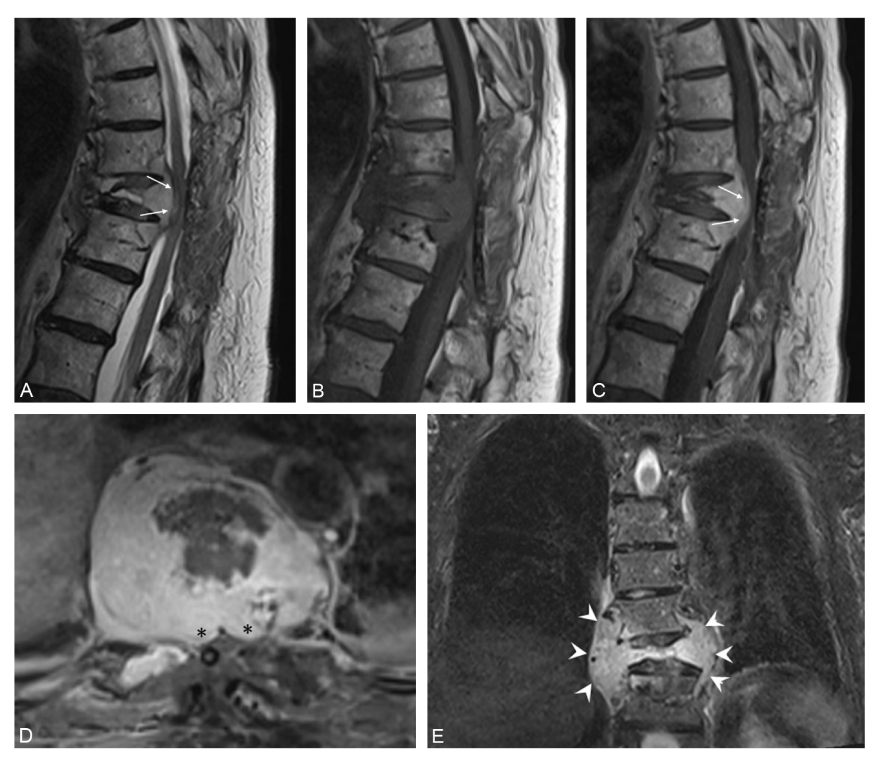

Fig. 52.2. Métastase vertébrale thoracique (cause extradurale).

IRM en coupes sagittales pondérées en T2 (A), en T1 sans (B) et après injection de gadolinium (C), et axiales (D) et frontales (E) pondérées en T1 après injection de gadolinium avec saturation des graisses. Tassement vertébral avec recul du mur postérieur (flèches) et compression médullaire de type extradural. Rehaussement après injection du tissu tumoral avec extension épidurale antérieure (∗) et paravertébrale (têtes de flèche) bilatérale, bien visible respectivement en coupes axiale et frontale.

Source : CERF, CNEBMN, 2022.